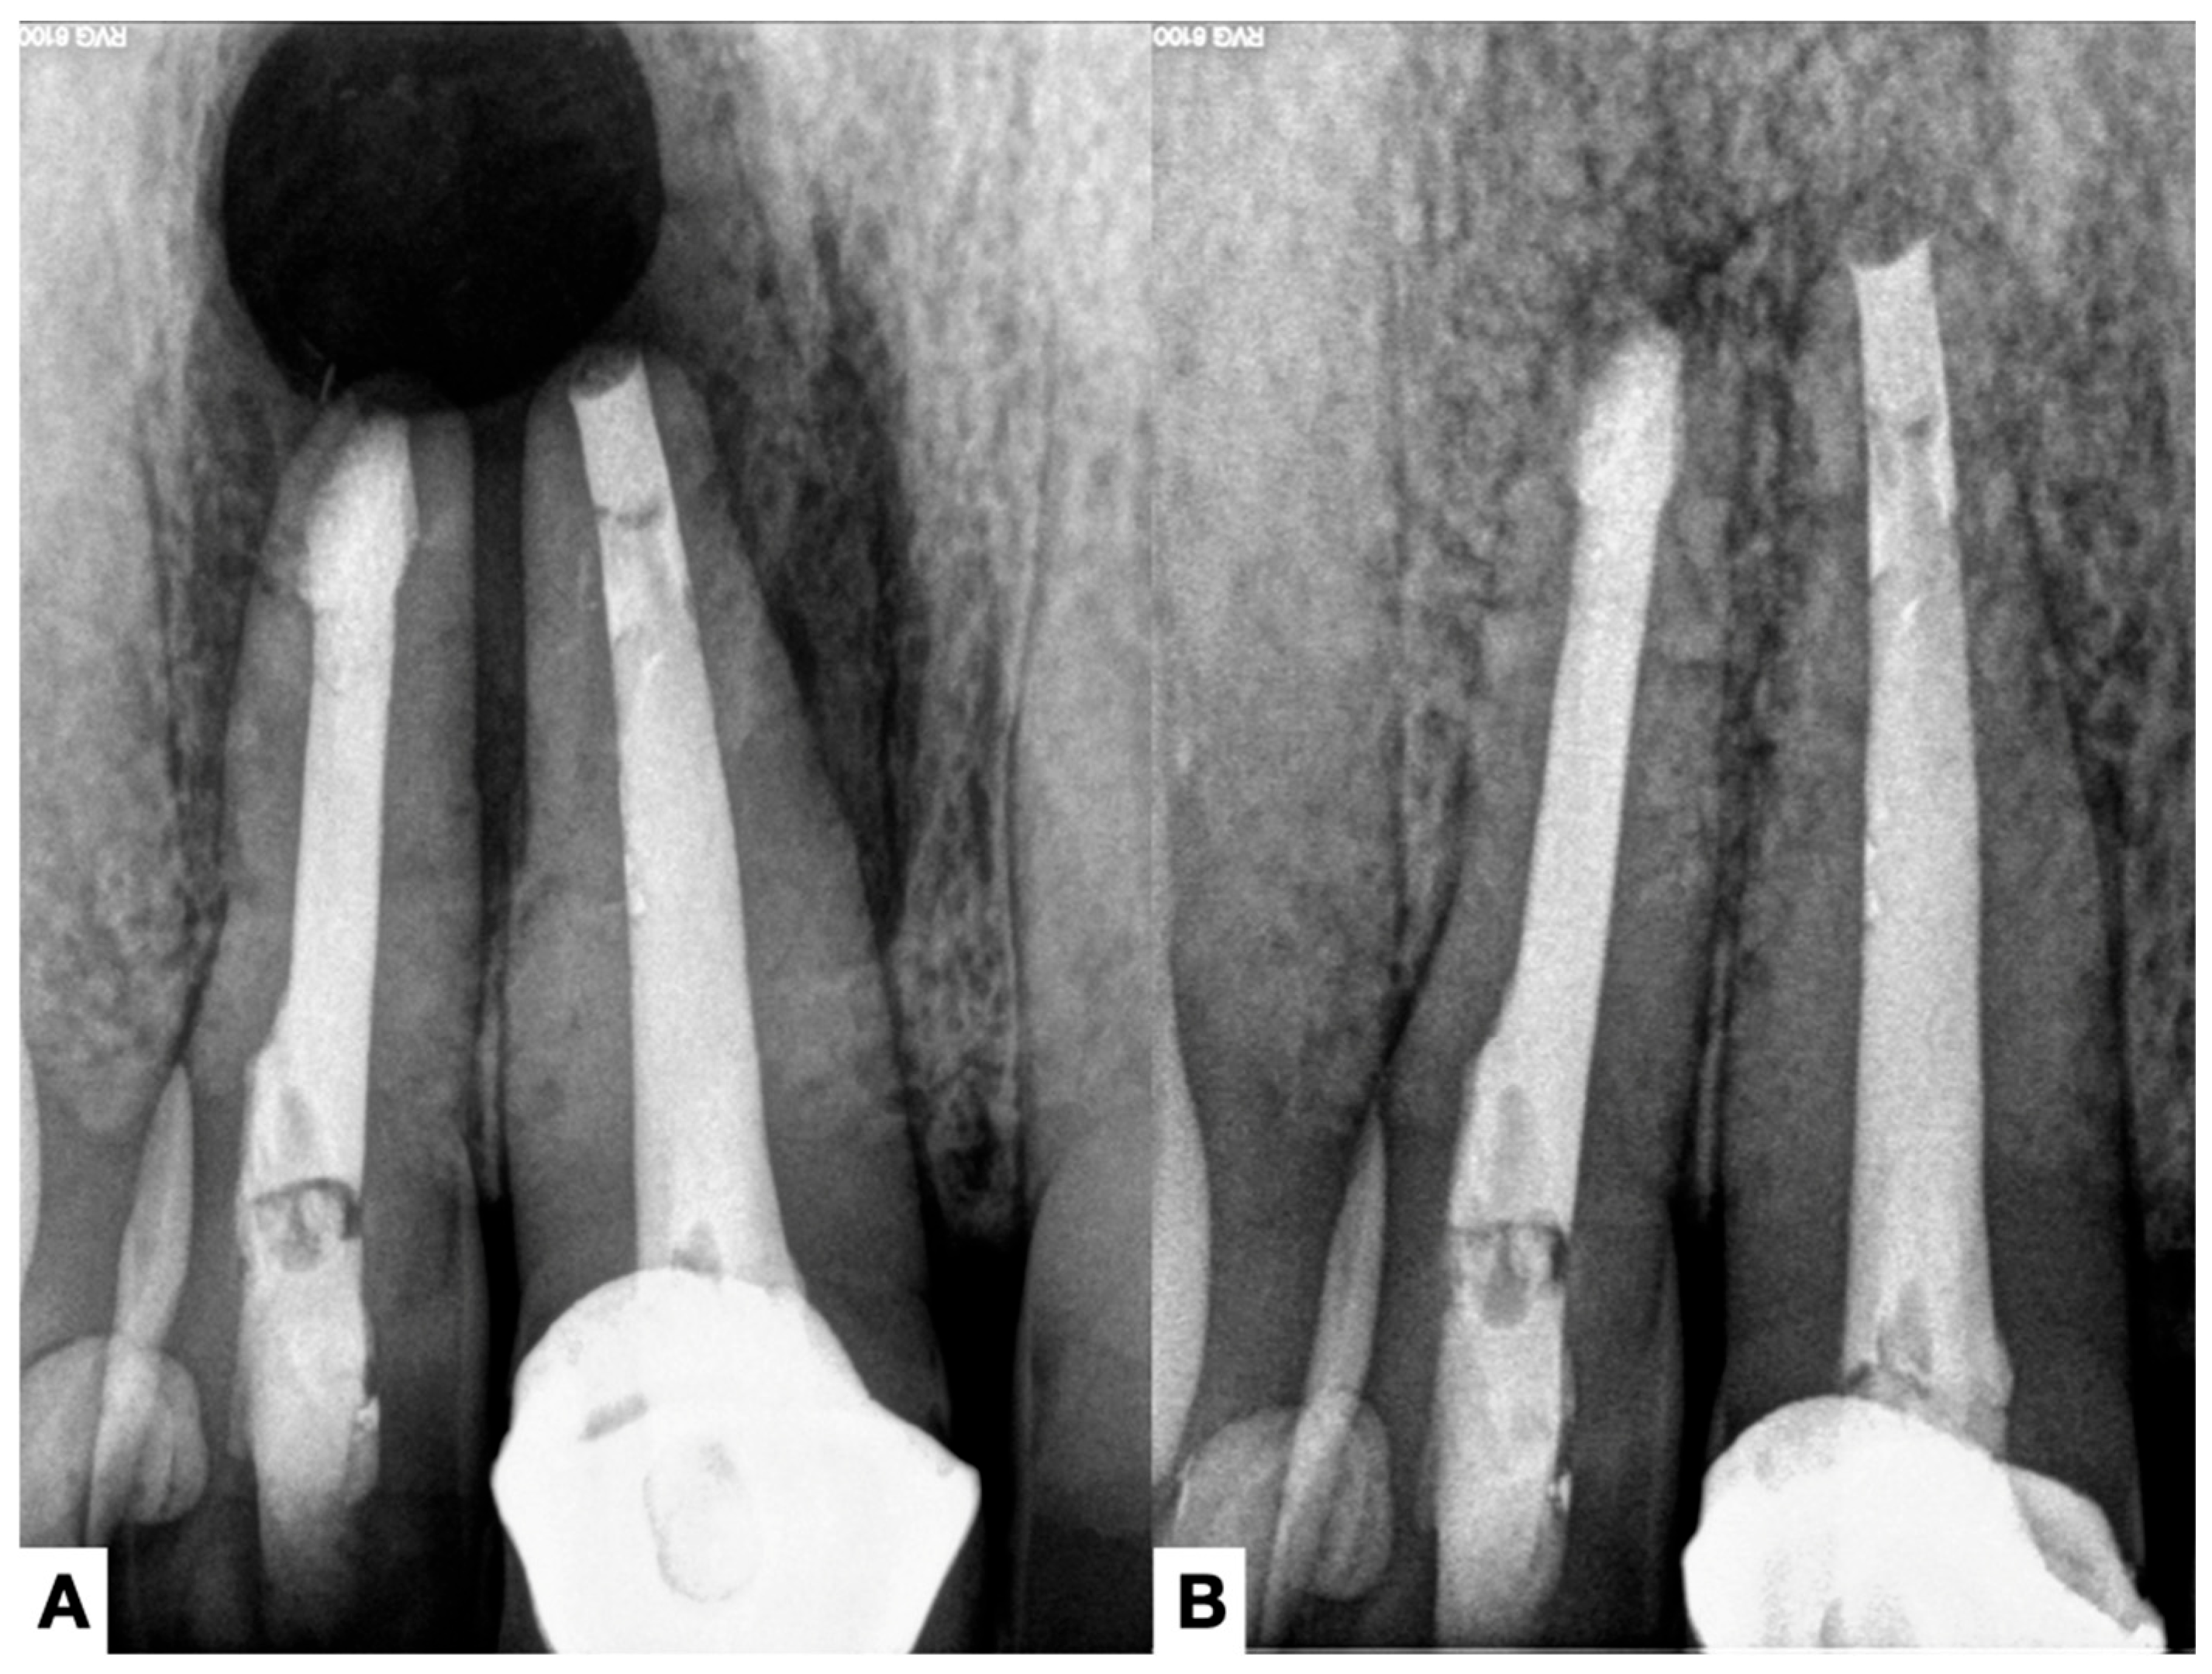

4.3. Radiographic Assessment

- Ricucci, D.; Candeiro, G.T.; Bugea, C.; Siqueira, J.F., Jr. Complex Apical Intraradicular Infection and Extraradicular Mineralized Biofilms as the Cause of Wet Canals and Treatment Failure: Report of 2 Cases. J. Endod. 2016, 42, 509–515. [Google Scholar] [CrossRef]

- Ricucci, D.; Martorano, M.; Bate, A.L.; Pascon, E.A. Calculus-like deposit on the apical external root surface of teeth with post-treatment apical periodontitis: Report of two cases. Int. Endod. J. 2005, 38, 262–271. [Google Scholar] [CrossRef]

- Petitjean, E.; Mavridou, A.; Li, X.; Hauben, E.; Cotti, E.; Lambrechts, P. Multimodular assessment of a calcified extraradicular deposit on the root surfaces of a mandibular molar. Int. Endod. J. 2018, 51, 375–385. [Google Scholar] [CrossRef]